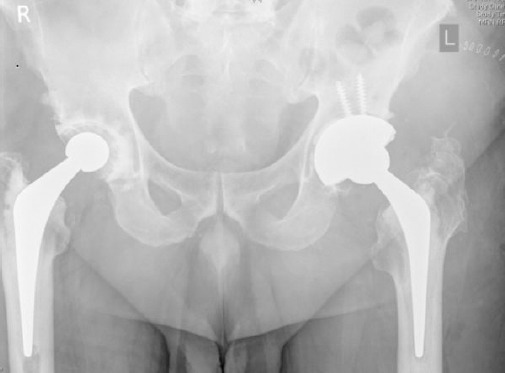

Figure 4.

Immediate Post-operative (Left)

The above radiographs are of a 59 year old gentleman operated previously for bilateral hip replacements, with the left hip being revised for acetabular component loosening. The femoral component was revised as well due to evidence of intra-operative loosening of the femoral stem.

Figure 5.

3.5 years Post-operative